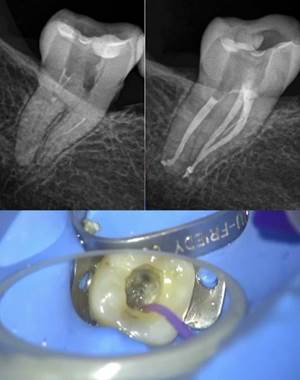

Imagen clínica bajo microscopio durante el acceso a un molar mandibular con una anatomía poco frecuente que presenta 3 conductos en la raíz mesial.

Radiografía inicial de un 1.6 e imagen de microscopio con la entrada a los conductos obturada.